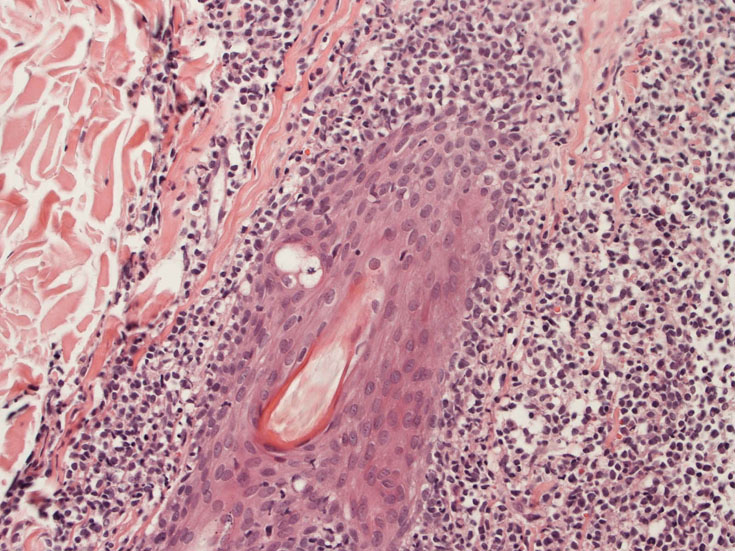

罹患リンパ節の基本構造は消失し腫瘍細胞のびまん性増殖で置換されている。非腫瘍性の小リンパ球(CD3+, CD4/8+)が濾胞様に散在して残る(Fig.01)。不整型または類円形の明るい核をもつmedium-sizeのリンパ球様細胞が密に増殖している。細胞質は乏しい(Fig.02)。CD68陽性macrophageが多く混在する部分が認められた(Fig.03)。

Fig04, Fig05は腫瘍細胞の拡大像。大型異型細胞の出現が認められる。腫瘍細胞はCD4+, CD56+, CD123+(Fig.06)